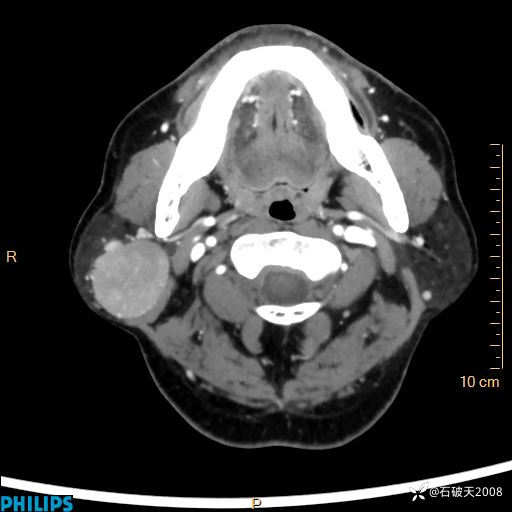

动脉期